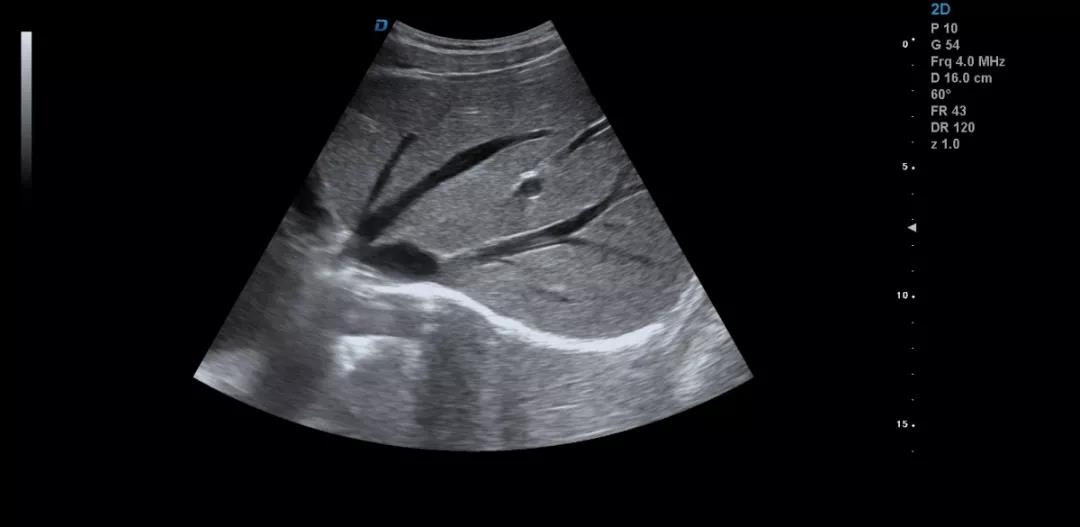

眾所周知,肝臟有很多檢查死角,成為超聲檢查的盲區,如肺和骨所掩蓋處,肝右前上段及右后上段的膈頂部,左外葉外側角區,沿肝臟表面的肋骨下區等等部位,只有極其細致的檢查配上精巧的手法才能盡可能的顯示清楚這些部位。

如果我們能夠細致的檢查每個病人,所謂的肝臟死角能夠盡可能的探測到,肝臟的死角其實只有膈頂部,其他的部位如果能細致檢查都可以探測到。

肝左葉掃查時,矚患者深吸氣,可以盡量使肝下移,更接近體表,顯示清楚,掃查至外側角肝臟消失的位置。然后探頭連續滑動,沿肋緣下斜切,矚患者深吸氣,探頭做扇形掃查,盡可能側動探頭至與皮膚平行,肝臟的絕大部分病變不會被遺漏。

對于肥胖體型或腹腔臟器明顯的,這種方法就不合適,可以采取肋間斜切的方法,自下而上逐個肋間連續掃查,注意不要做跳躍式掃查,這樣容易眼花也容易遺漏病變。

肝臟膈頂部掃查體會:

1)一般是讓患者深吸氣,讓肝臟下移,然后探頭盡量上翹;

2)當然很多患者因肥胖或肺氣的干擾會顯示更差,這時我就讓患者深呼氣,把氣全部吐干凈,然后屏氣掃查;

3)還有就是不要沿著肋間隙掃查,而是和肋間隙成一定的角度緩慢向右上方腋前線掃查;

4)在平臥位掃查時,在橫切腎臟時探頭盡量上翹,甚至與腹壁平行,當然在右側肋緣下也行;

5)變換體位掃查,肝臟因重力作用產生移位。左側臥位、右側臥位、各種斜位、還有站立位等等。

掃查肝臟時要配合患者的呼吸運動,采取你動我靜,你靜我動的掃查方法,并最大限度的側動探頭,最大角度的顯示肝臟。

發現肝臟病變時要多切面多角度掃查,可以了解病變的解剖位置并排除假陽性。